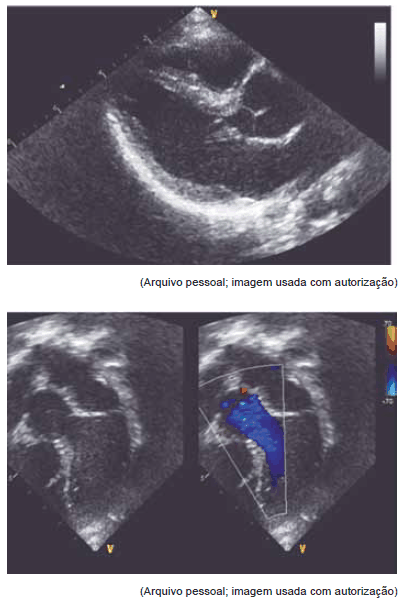

Estas imagens de ecocardiograma dizem respeito a paciente com síndrome

Provas